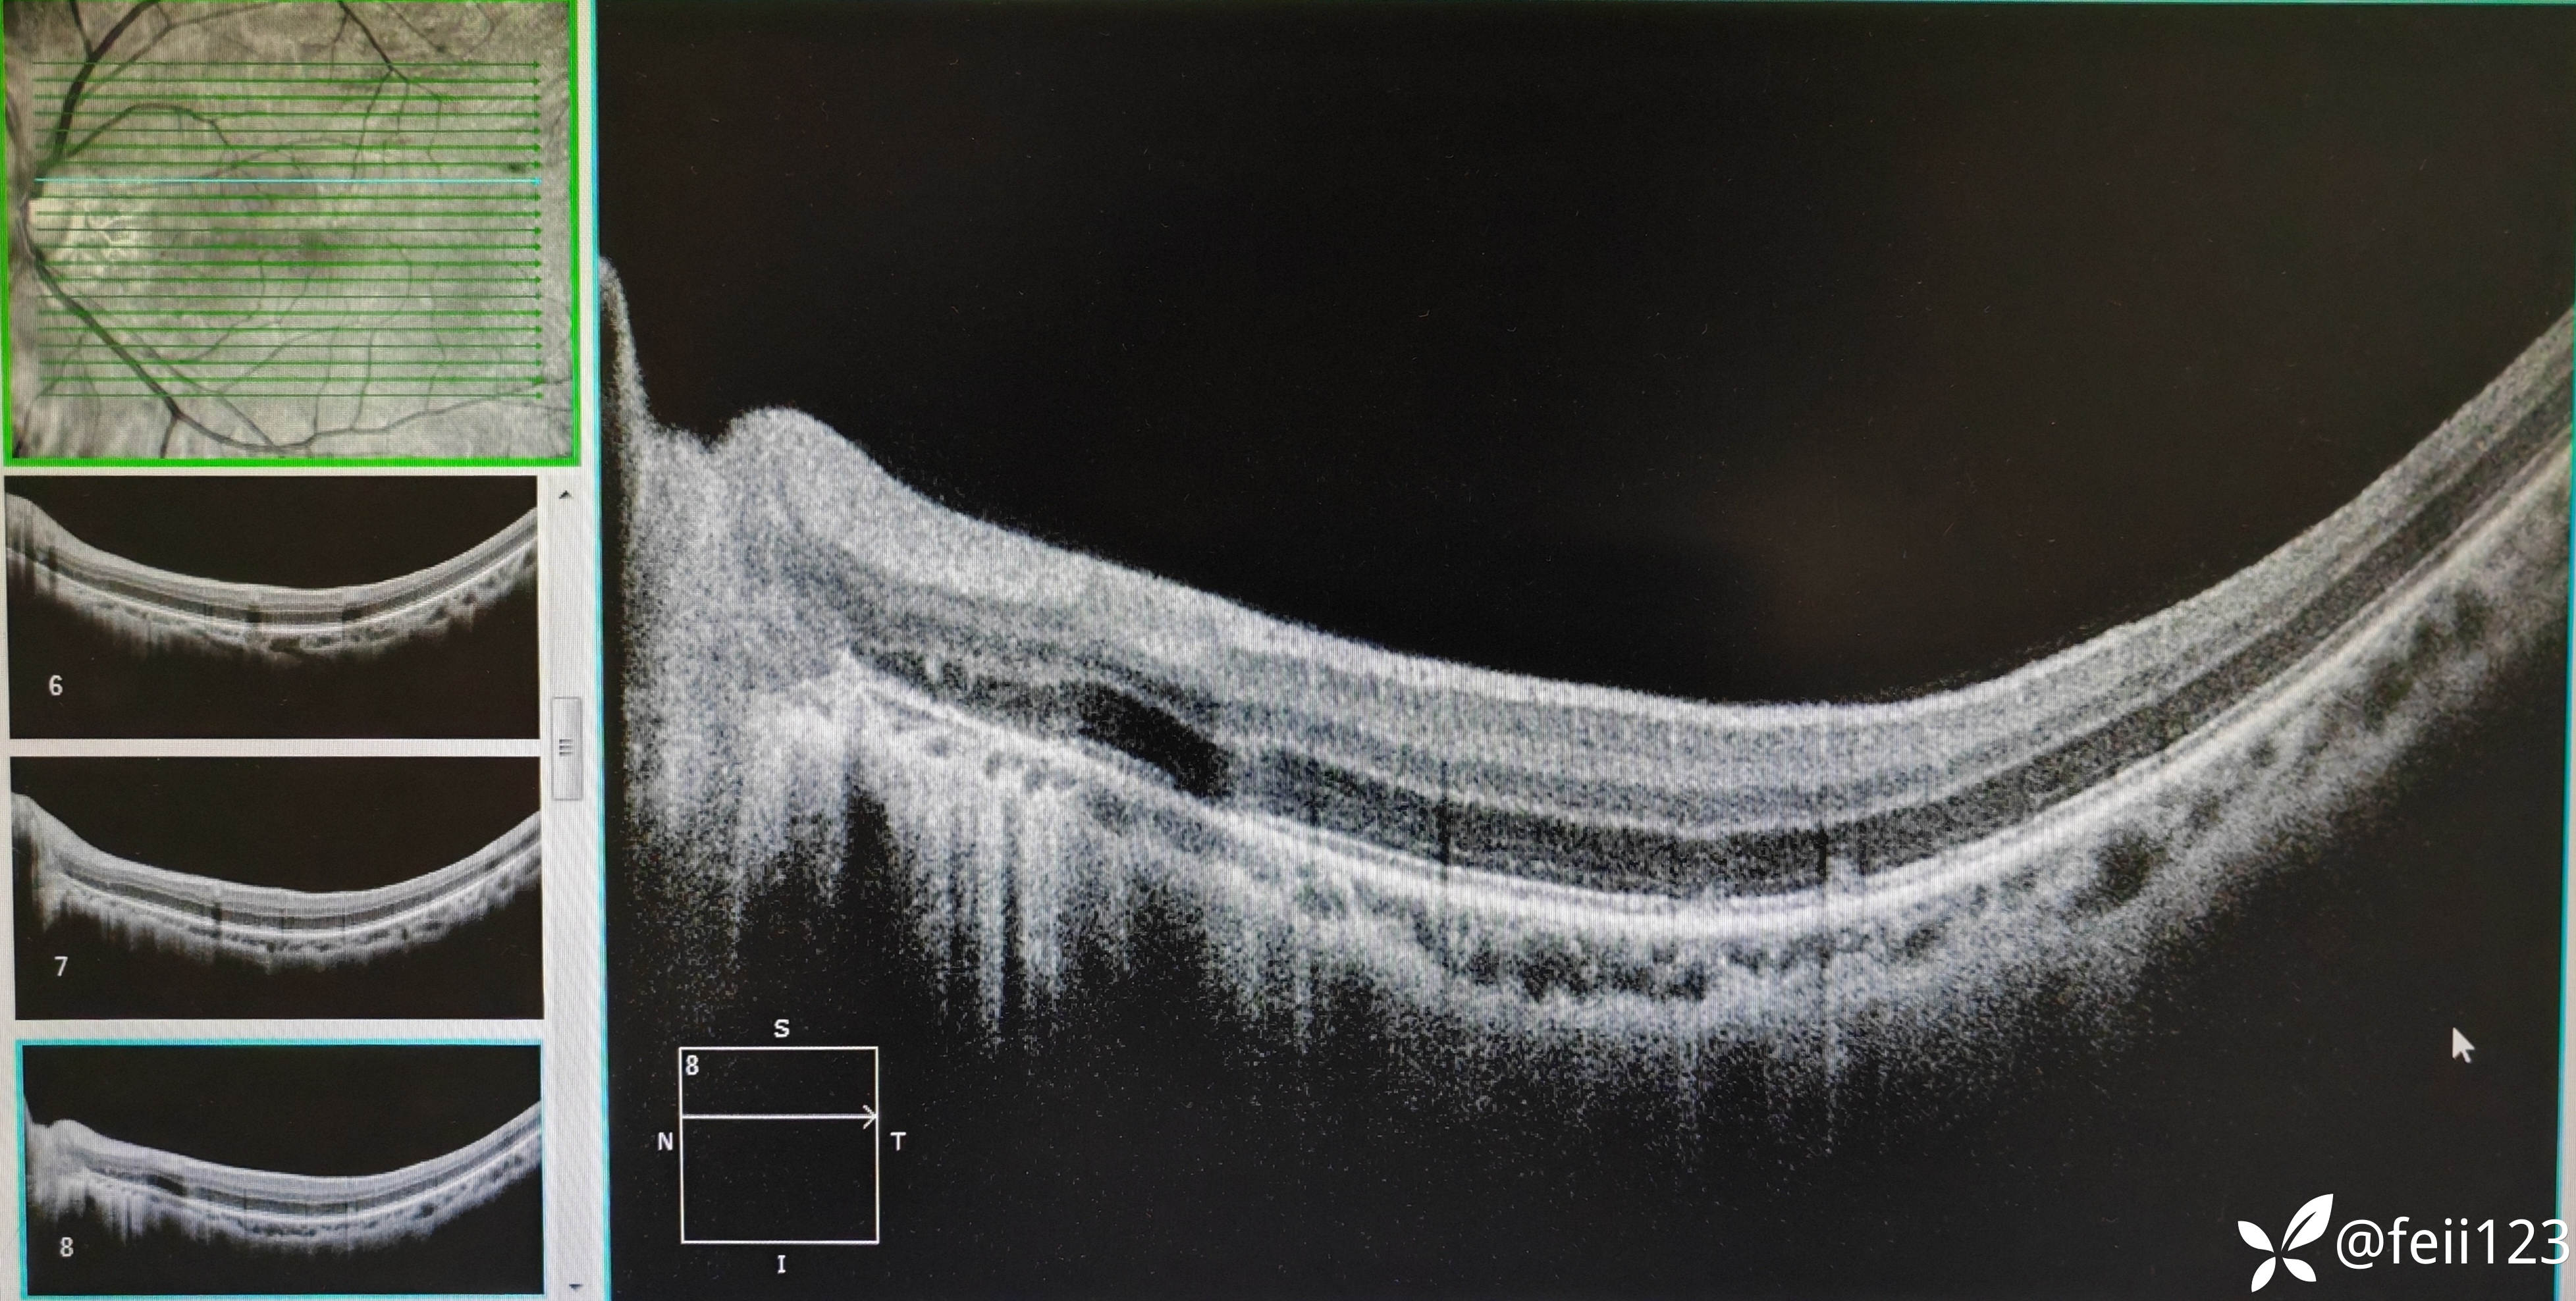

【检查】矫正视力右眼1.0左眼0.4,眼压正常15 16,眼前段未见异常,玻璃体清,眼底如图,左眼底可见后极部及鼻侧周边多个白点。